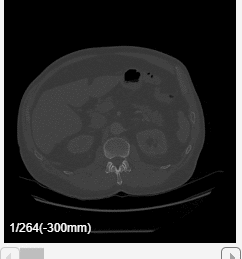

The app displays volumes as 2-D slice planes and a 3-D volume in a four-pane view. The 2-D slices are displayed in the Transverse, Sagittal, and Coronal planes. If your volume has incomplete or oblique spatial metadata, the app displays the volume without anatomical labels.

View 2-D Slices

To explore the volume, zoom in on a slice pane using the scroll wheel or the zoom controls in the top-right corner of the slice. Navigate between slices by using the scroll bar in each of the 2-D slice panes. The app also displays anatomical display markers indicating the anterior (A), posterior (P), left (L), right (R), superior (S), and inferior (I) directions. Labels in the bottom-left corner of each slice pane indicate the slice position in world coordinates, the current slice number, and the total number of slices in that dimension. When you display multiple volumes or labels as an overlay, the app hides the slice numbers and shows only the position values. The bottom of the app window displays information about the pixel beneath the pointer, including its coordinates and intensity. Note that, if you import a volume with limited spatial metadata, the app hides the anatomical display markers.

For this example, specify these values to create an animation that captures every eighth slice along the transverse direction.

Specify the Slice Direction as

Transverse.Keep the default values for the minimum and maximum of Slice Range as

1and264, respectively.Keep the default values for the minimum and maximum of Position as

-300and27, respectively.Specify the step size as

8 frames.Select Append animation in reverse so each loop animates forward and then in reverse through the slice range.